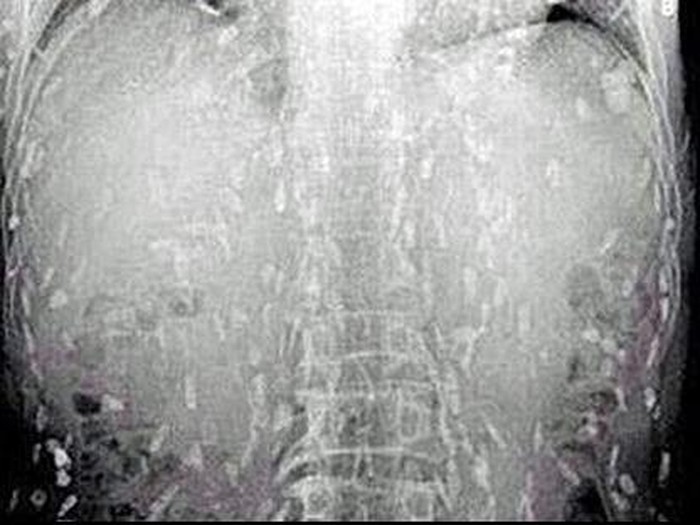

4. Pasien pria asal Guangxi

|

foto: Rocketnews24

Ternyata pria ini suka meminum darah dari babi hidup, dan sekali minum ia bisa menandaskan beberapa gelas sekaligus. Di China, darah babi segar kerap diolah menjadi sup manis.